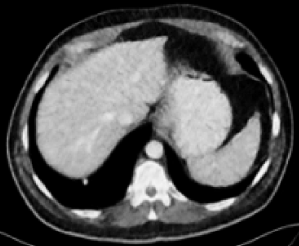

| LDCT (0.7586) | FDCT |

RED-CNN (0.8790)

| RED-CNN+SSWL (0.8901) | RVAE (0.8851) | RVAE+SSWL (0.9023) |

Figs. 3 and 4 demonstrate precise removal of noise from whole scans as well as specific regions of interest (ROIs), proving the effectiveness of our model over baseline architectures and other self-supervised tasks. As shown, both the RVAE and SSWL are able to quantitatively and qualitatively outperform their respective counterparts.